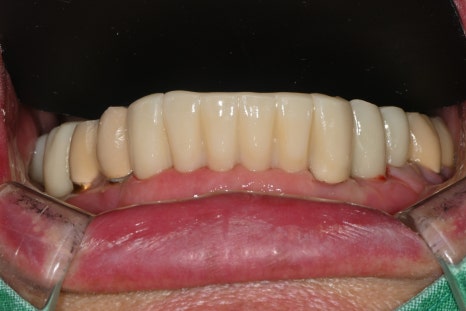

왼쪽 사진: 윗니 보철은 전체적으로 고정성이 좋고 교합이 안정적으로 설계되었습니다.

오른쪽 사진: 발치한 자리에 식립한 임플란트에 최종 보철이 정확히 체결된 모습입니다.